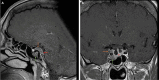

Background: Invasion of the CS is one of the limiting factors for total resection for PitNet tumors with cure rates less than 30%. Extended approaches may be considered in selective and well-studied cases of secreting adenomas.

Method: We describe the key steps of the endoscopic transcavernous approach for functional pituitary adenomas with a video illustration. The surgical anatomy is described along with the advantages and limitations of this approach.